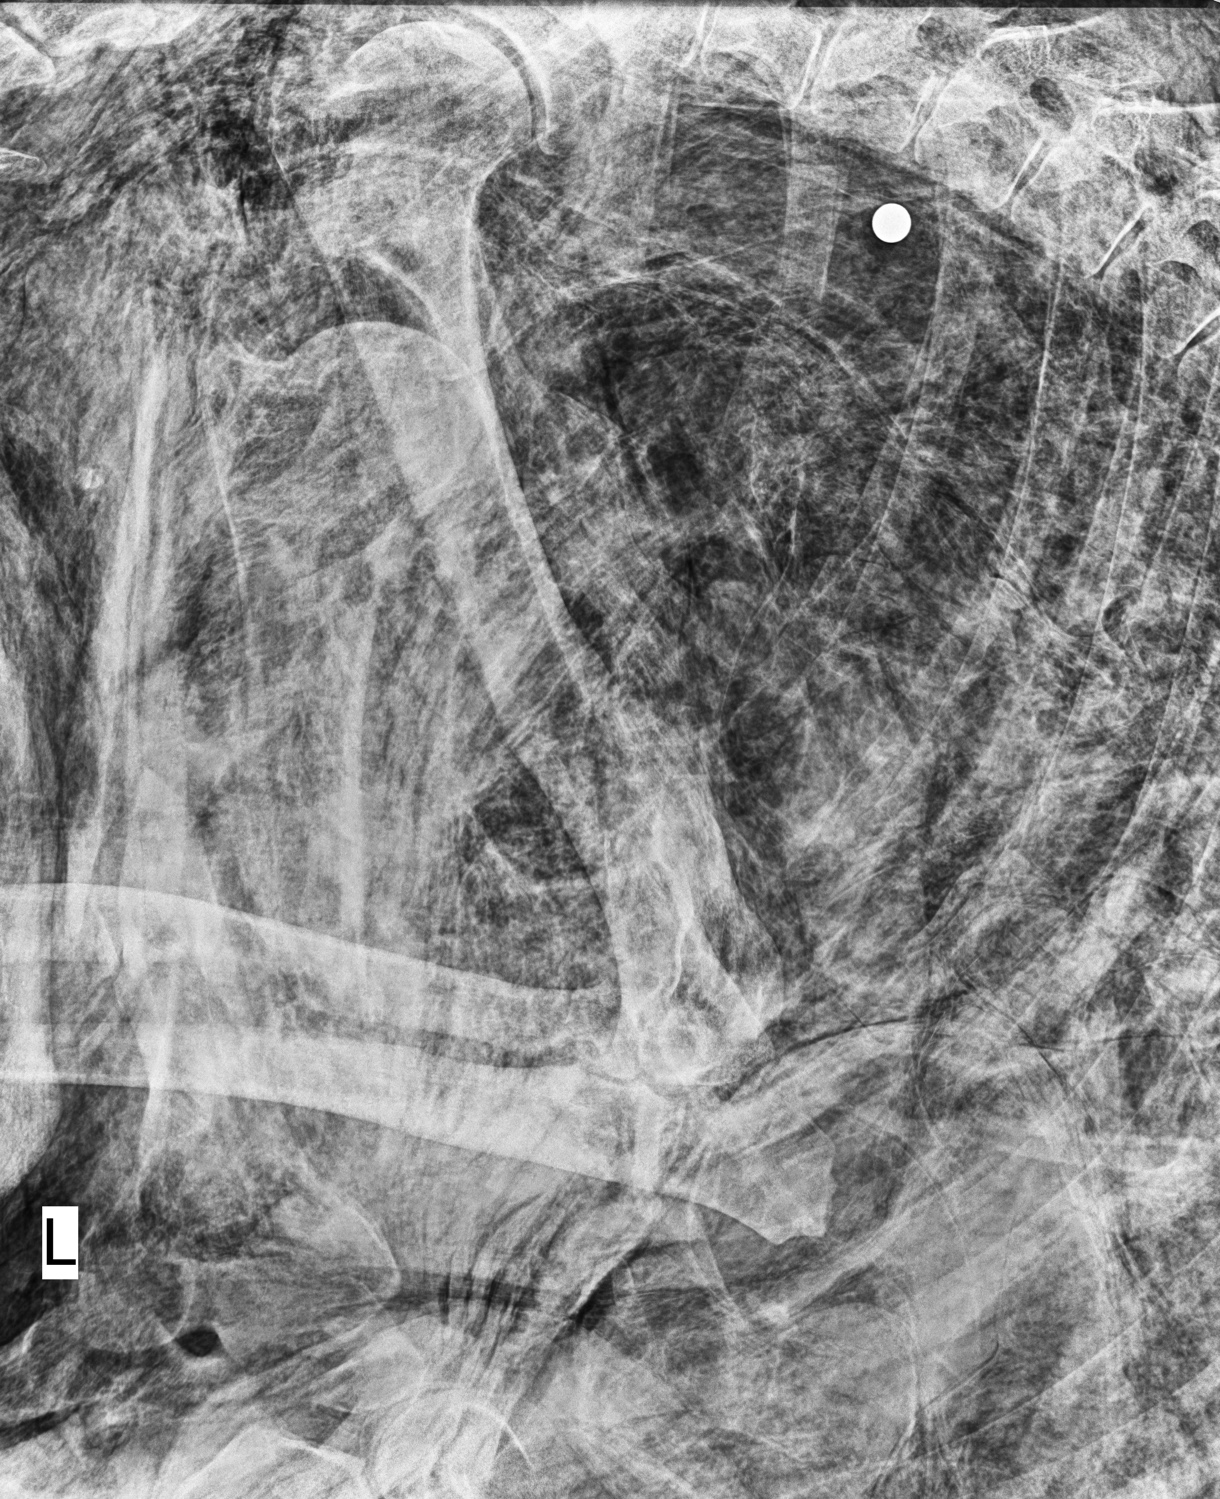

內政部國家公園署玉山國家公園管理處(下稱玉管處)的保育巡查員於四月底進行瓦拉米步道的巡查時,在山風二號吊橋下的瀑布旁發現有死亡黑熊的個體。該個體由玉管處送往屏東科技大學獸醫系動物疾病診斷中心解剖檢驗後,發現為玉管處於110年度委託國立屏東科技大學黃美秀教授團隊繫放追蹤的個體,研究項圈編號BB03,且於左側胸腔背側檢驗出致死之子彈。根據遺體腐爛狀態推斷,編號BB03黑熊發現時已死亡三日以上。其死亡之位置距離國家公園邊界僅有300公尺,無法排除夜間盜獵之可能性,本案已移送保七總隊進行偵辦。國家公園區域內禁止任何狩獵活動,對此玉管處除深感遺憾,將持續加強與警政署保七總隊第六大隊的聯合查緝,步道及公路上重要路口架設車輛辨識系統等工作,以降低此類憾事發生。